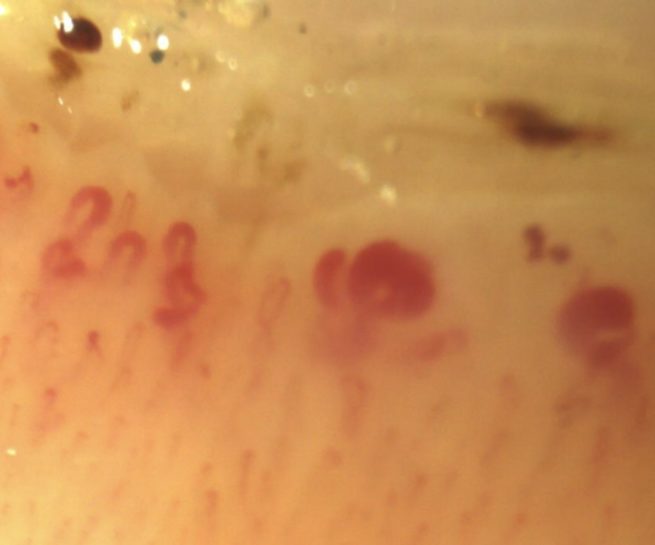

Il traite à la fois des pathologies fréquentes et rares des artères (artériopathie, anévrysmes, maladies génétiques, vascularites), des veines (embolie pulmonaire et thrombose veineuse profonde, varices, thrombophilies, malformations veineuses), de la microcirculation (Raynaud, engelures, livedo…) des lymphatiques (lymphœdèmes, malformations) et les plaies chroniques (ulcères, plaies du pied diabétique, escarres…)